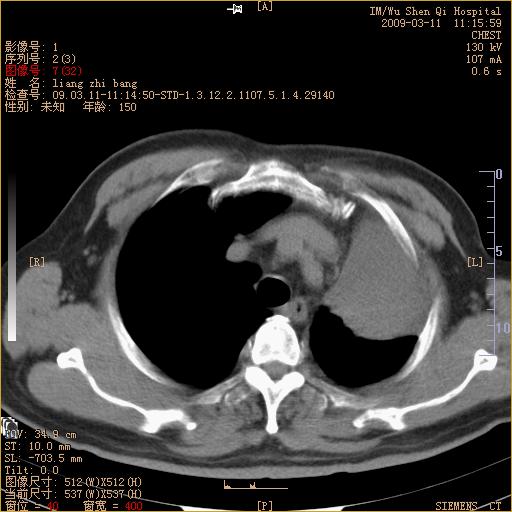

标题: CT18604:男,60岁,咳嗽一月余 [打印本页]

标题: CT18604:男,60岁,咳嗽一月余

1)考虑左肺上叶中央型肺癌并左肺上叶肺不张;建议必要时行纤支镜检查进一步明确诊断。2)左侧胸腔积液。

考虑左肺上叶中央型肺癌并左肺上叶肺不张

肺门肿块、支气管开口闭塞伴肺不张及胸水!典型的中心型肺癌变现!

1、左肺上叶中央型肺癌并上叶阻塞性肺不张。

2、左侧胸腔少量积液,右侧胸膜轻度增厚。

左肺们肿块并左肺上叶不张。考虑左肺中心性肺癌并左肺上叶不张及左侧胸腔积液